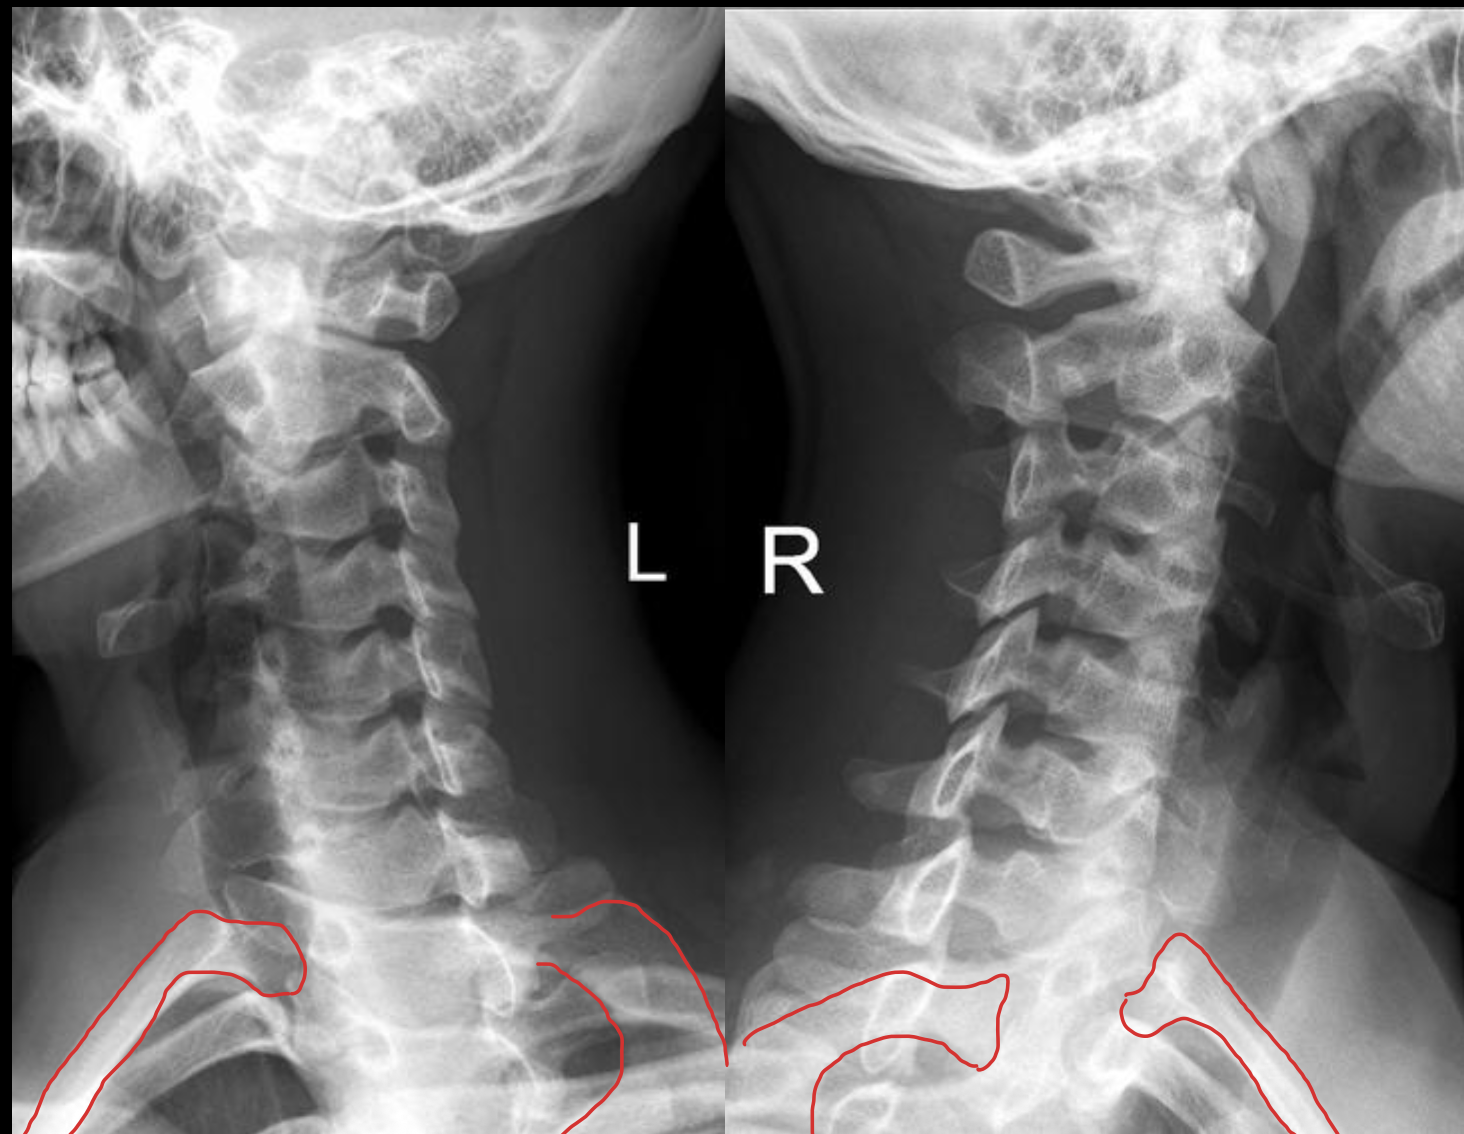

1st rib